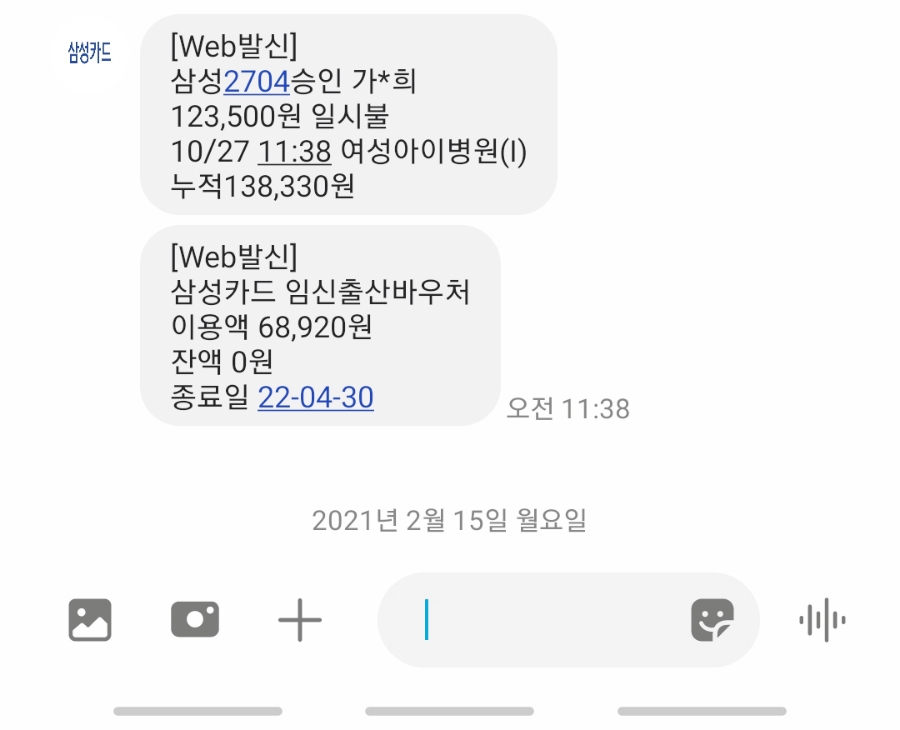

1차 기형아 검사 시기 비용

1차 기형아 검사 시기는 임신 10주에서 13주 사이에 이루어졌고, 저는 임신 12주에 검사를 했습니다.두 번째는 임신 중기의 15주~20주 사이에 실시합니다.결과는 2차 검사까지 모두 완료한 후 1차 2차 검사 결과를 합쳐서 최종 결과가 나옵니다.

1차 임신 기형아 검사 비용은 1,23500원이었습니다.혈액 검사와 초음파 검사까지 합쳐서 12만원대가 나온 것 같습니다.저는 고위험 산모와 병원에도 자주 가는 약주사약이 많아서 ㅠㅠ다른 사람의 출산 전까지 쓴다는 임신출산 바우처를 12주에 다 써버렸네요……잔액 0원..^^ㅋㅋㅋㅋ병원비는 정말 남들보다 5배는 쓴 것 같아서…